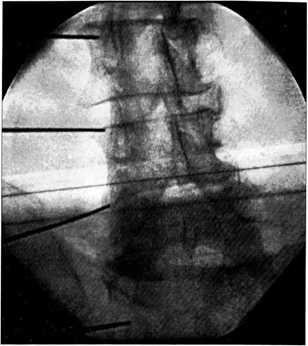

Рис. 4. Радиочастотная деструкция фасеточных нервов при сколиотической деформации грудного отдела позвоночника.

Результаты у 29 больных прослежены в сроки от 4 до 7 мес, у остальных период после манипуляции не превышает 3 мес. Во всех наблюдениях болевой синдром не рецидивировал, пациенты сохраняют высокую двигательную активность. Особенно интересен случай лечения спондилоартроза грудного отдела позвоночника у больной с диспластическим грудным сколиозом III—IV степени. Отсутствие эффекта от проводимой терапии и наличие болевого синдрома в течение последних 8 лет побудили нас к проведению радиочастотной денервации межпозвонковых суставов на вершине искривления с вогнутой стороны (рис. 4). Эффект был весьма впечатляющим: по шкале болевого аудита субъективный показатель интенсивности болевого синдрома снизился с 31 до 6 баллов. Необходимо также сказать, что мы не отметили никаких осложнений ни во время выполнения манипуляции, ни в раннем послеоперационном периоде.